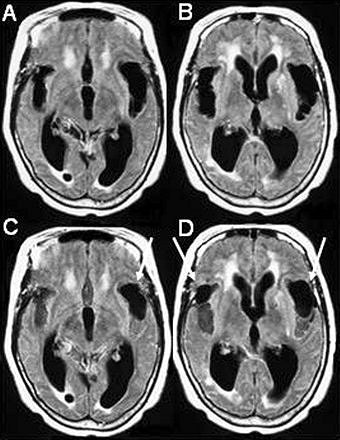

![]() |

| The advantage of using MRI to track NPH is that imaging can be done in any plane. MR is also more sensitive to interstitial, transependymal flow of cerebrospinal fluid, and hyperdynamic CSF flow seen with shunt-responsive NPH, as seen above (Neurosurgery Clinics of North America, October 2001, Vol. 12:4, pp. 661-684, viii). Image courtesy of Dr. William Bradley Jr., Ph.D. |